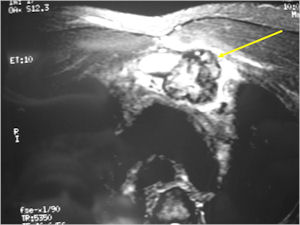

CT Scan:

- More useful for detecting mineralization and evaluating extent of bone destruction than plain X-ray

MRI:

- Also useful in determining extent

- There is often extensive edema around the tumor in the surrounding bone and soft tissues that can lead to a misdiagnosis of a malignant tumor.